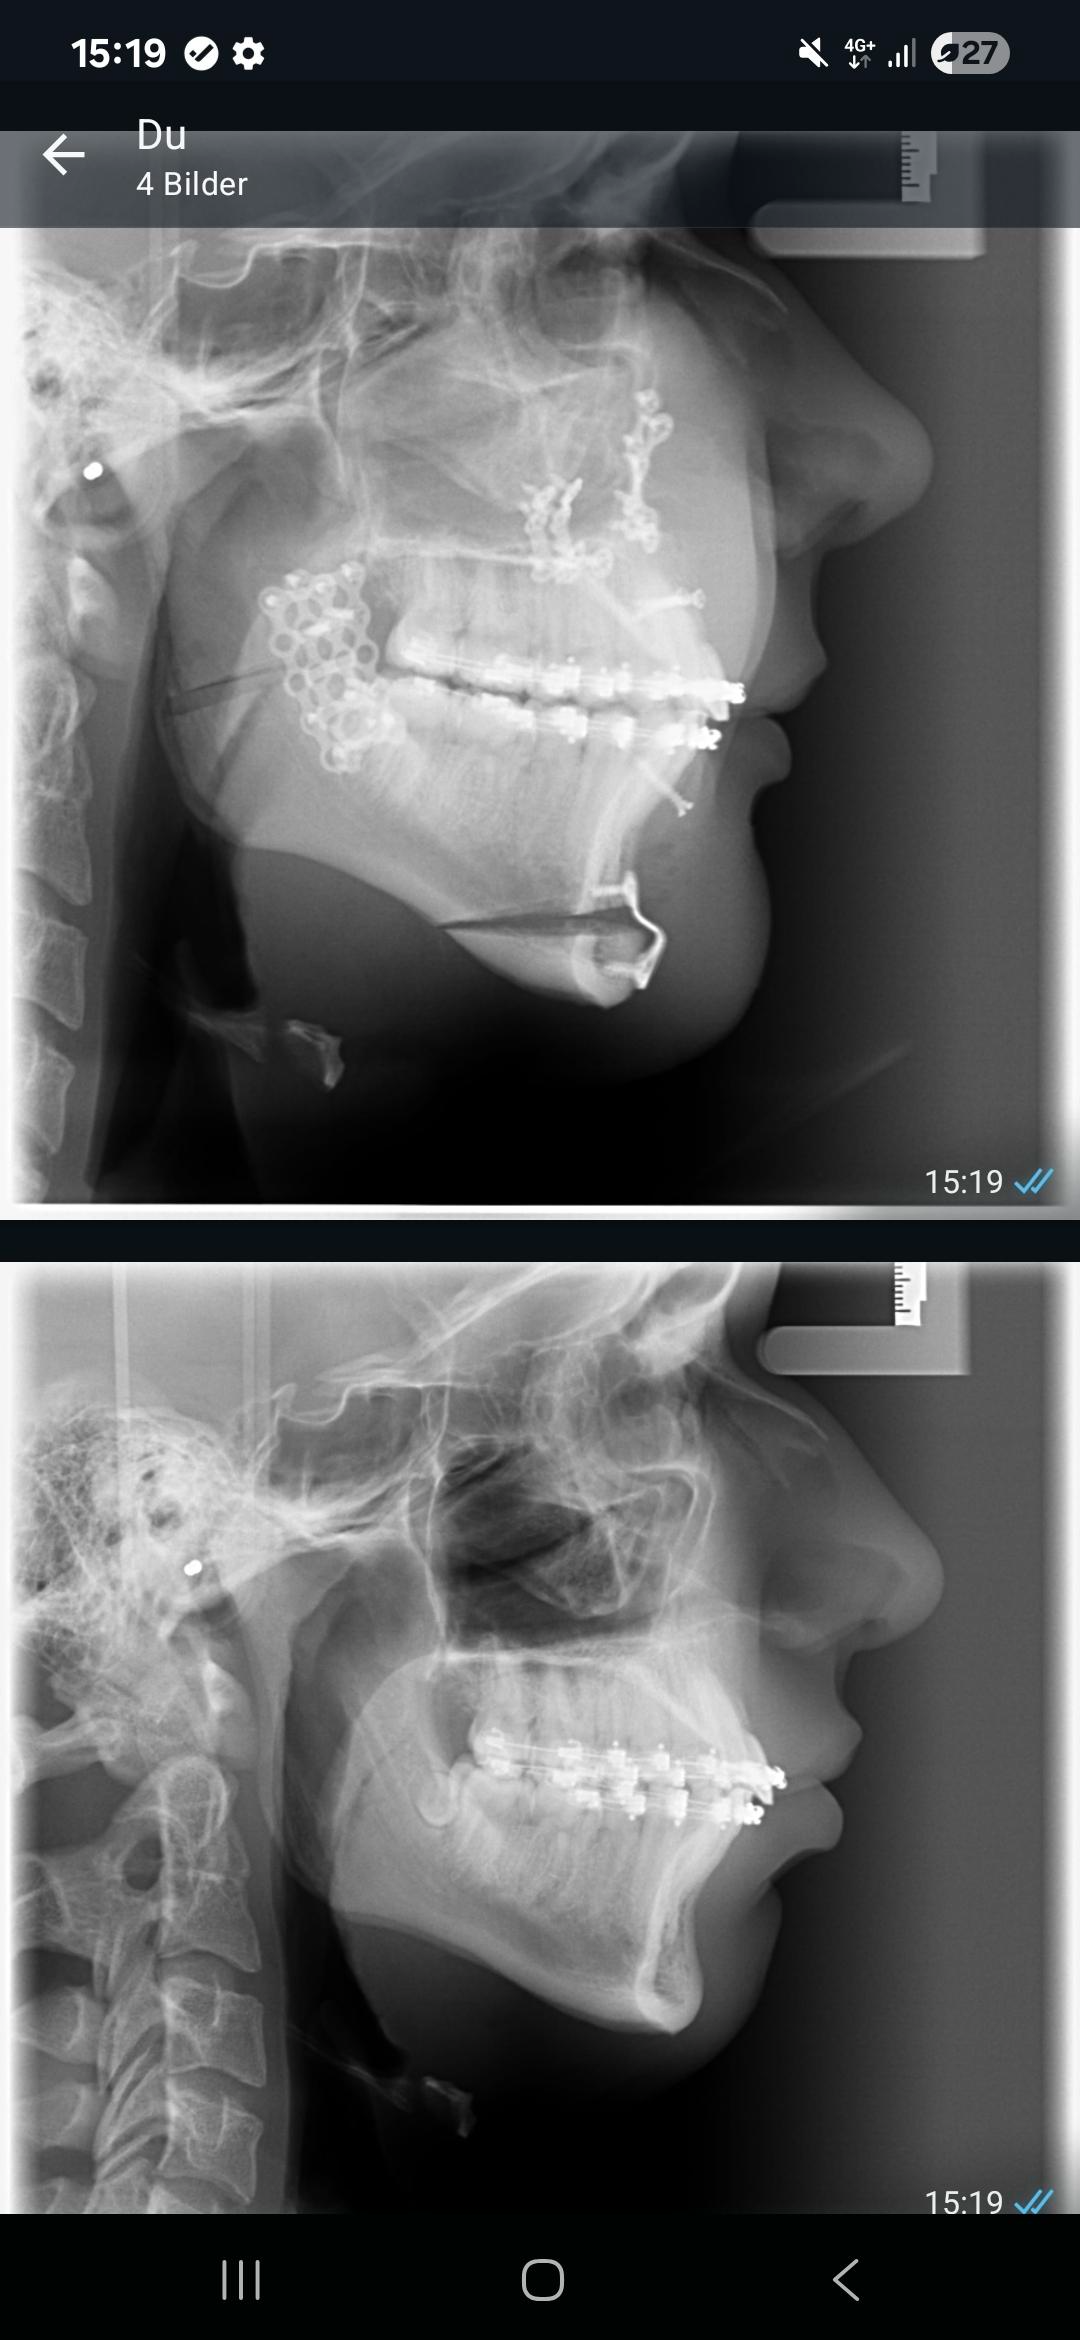

I had bimax 4.5 weeks ago and many people say my side ascended but my front descended a bit. I'm still bloated in the cheek area but not that bad. #

Will it go back to normal or could my front actually descend from the surgery`?

CT: